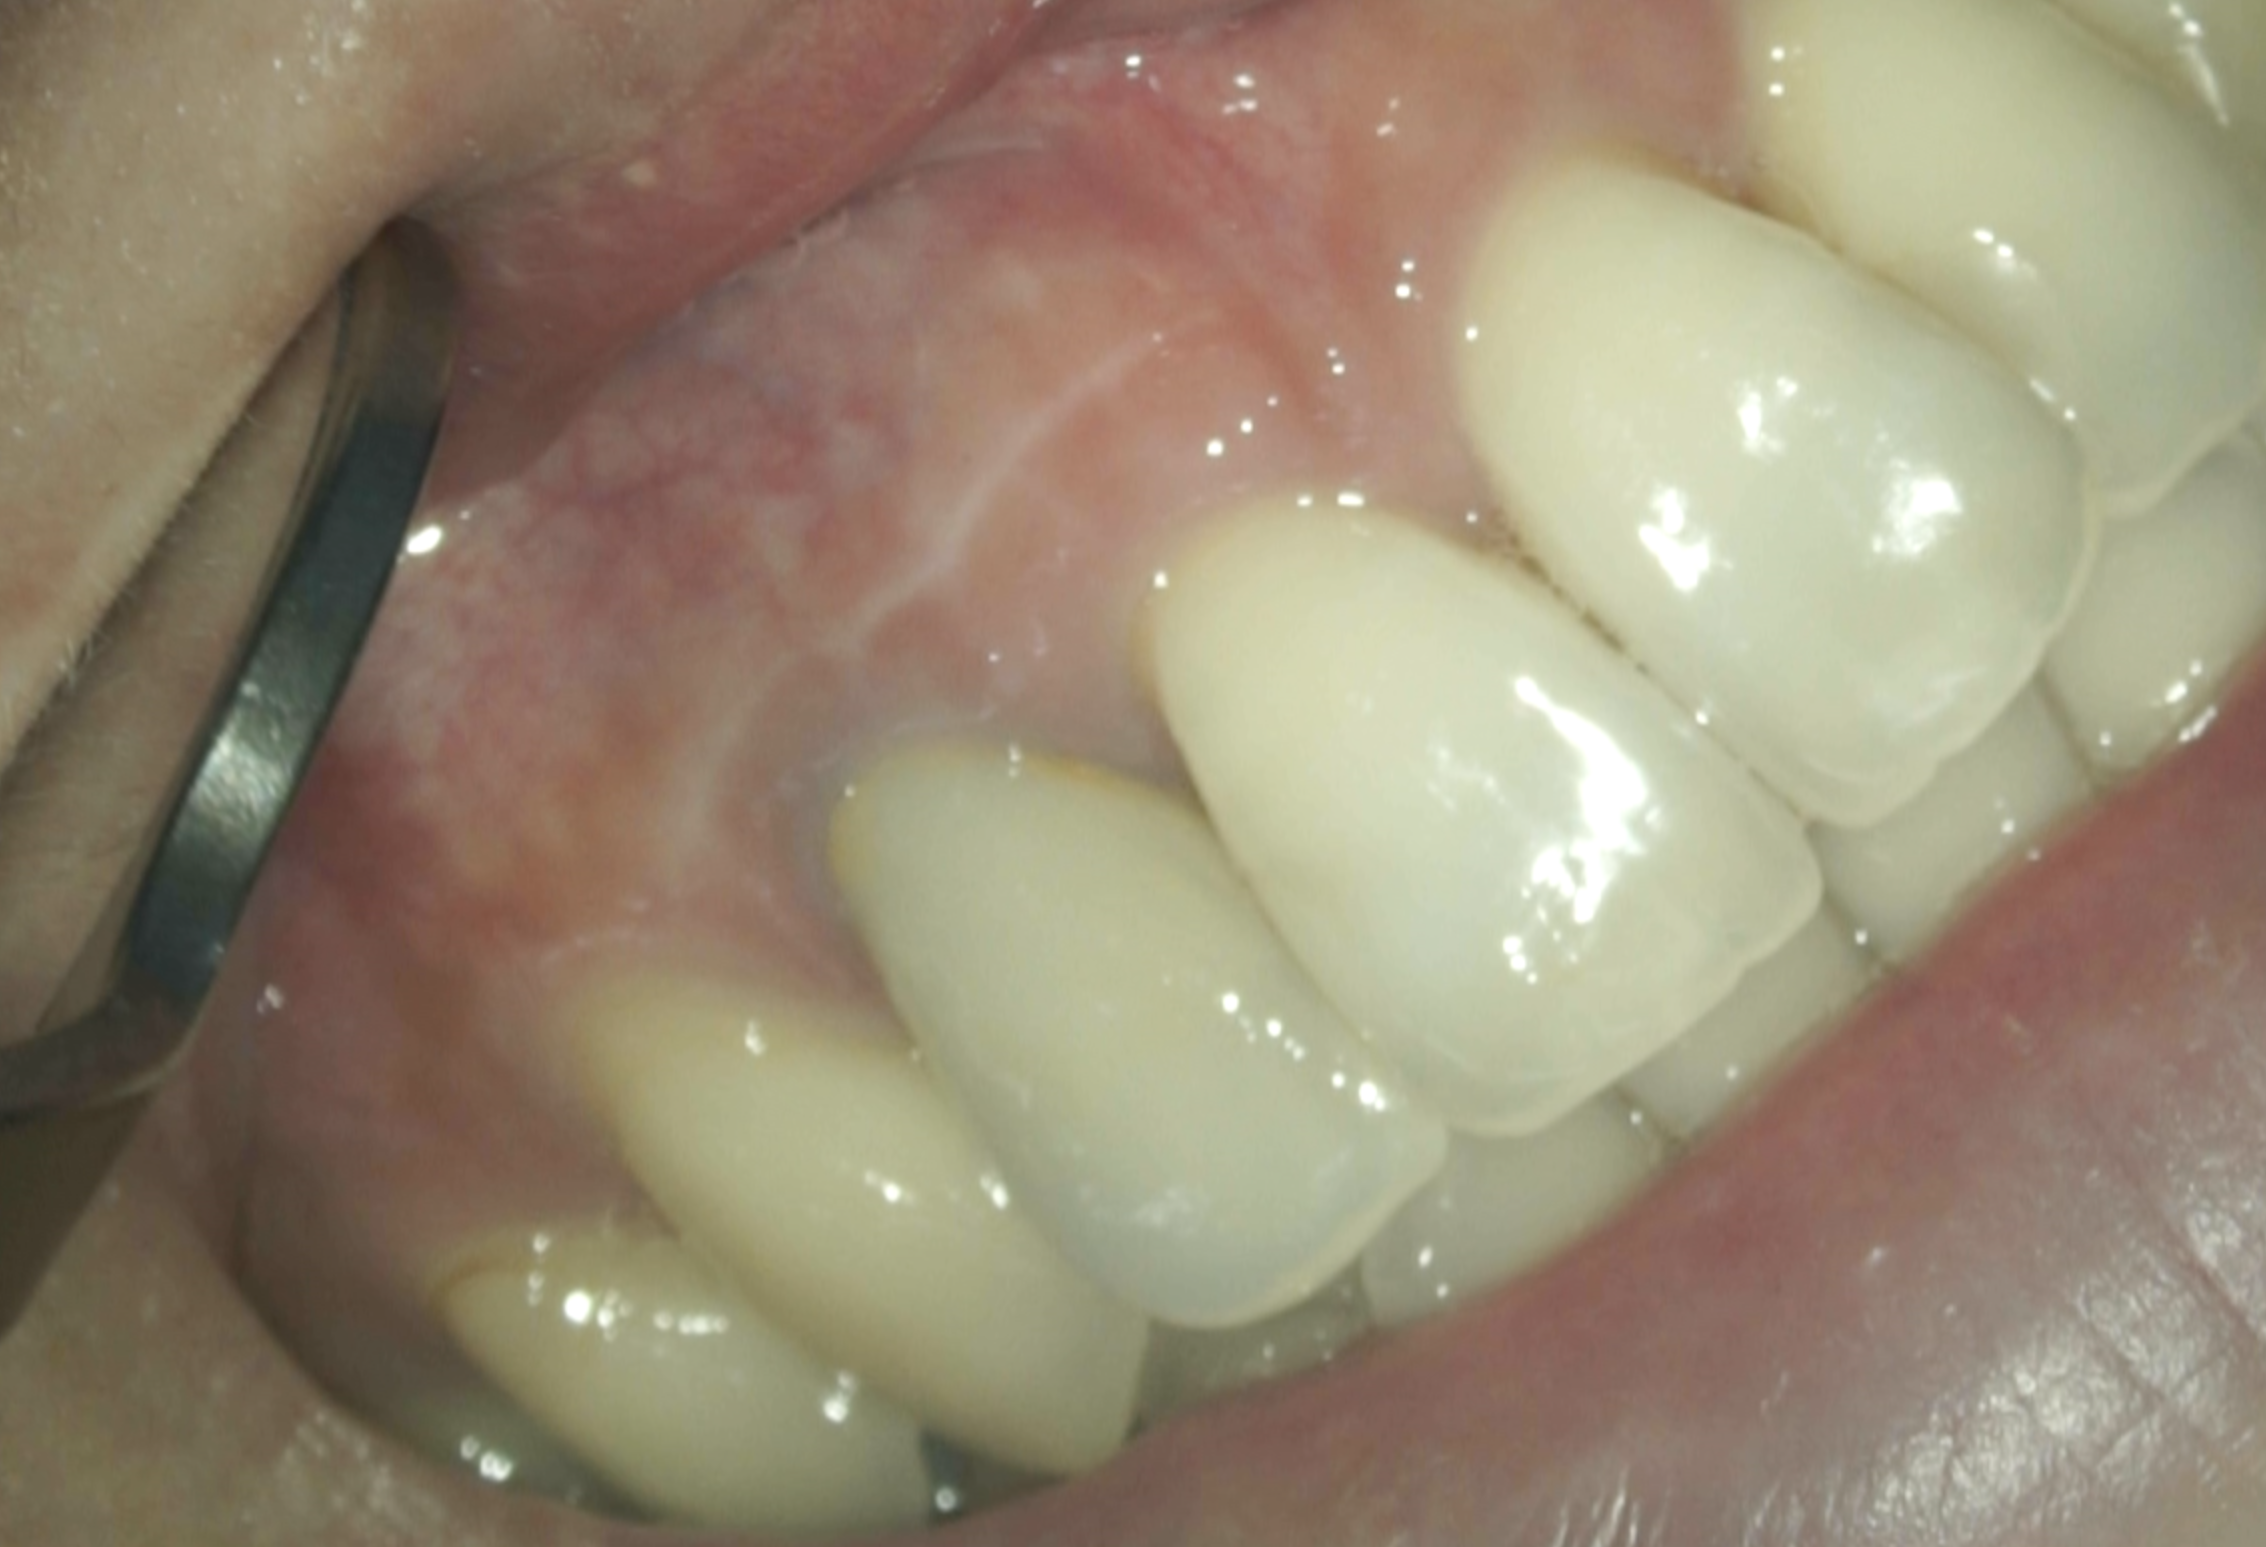

#7 Apicoectomy 1yr recall(2026.1.23)

瘢痕は若干残るが、患者さんは気にならないという。

もっとマージン付近で切開線を入れた方が良かったが、もはや仕方がない。

それは今後の改良点だろう。

初診時と比較した。

気泡は入ったが劇的に治癒し、臨床症状もないことからこの日で終診となった。